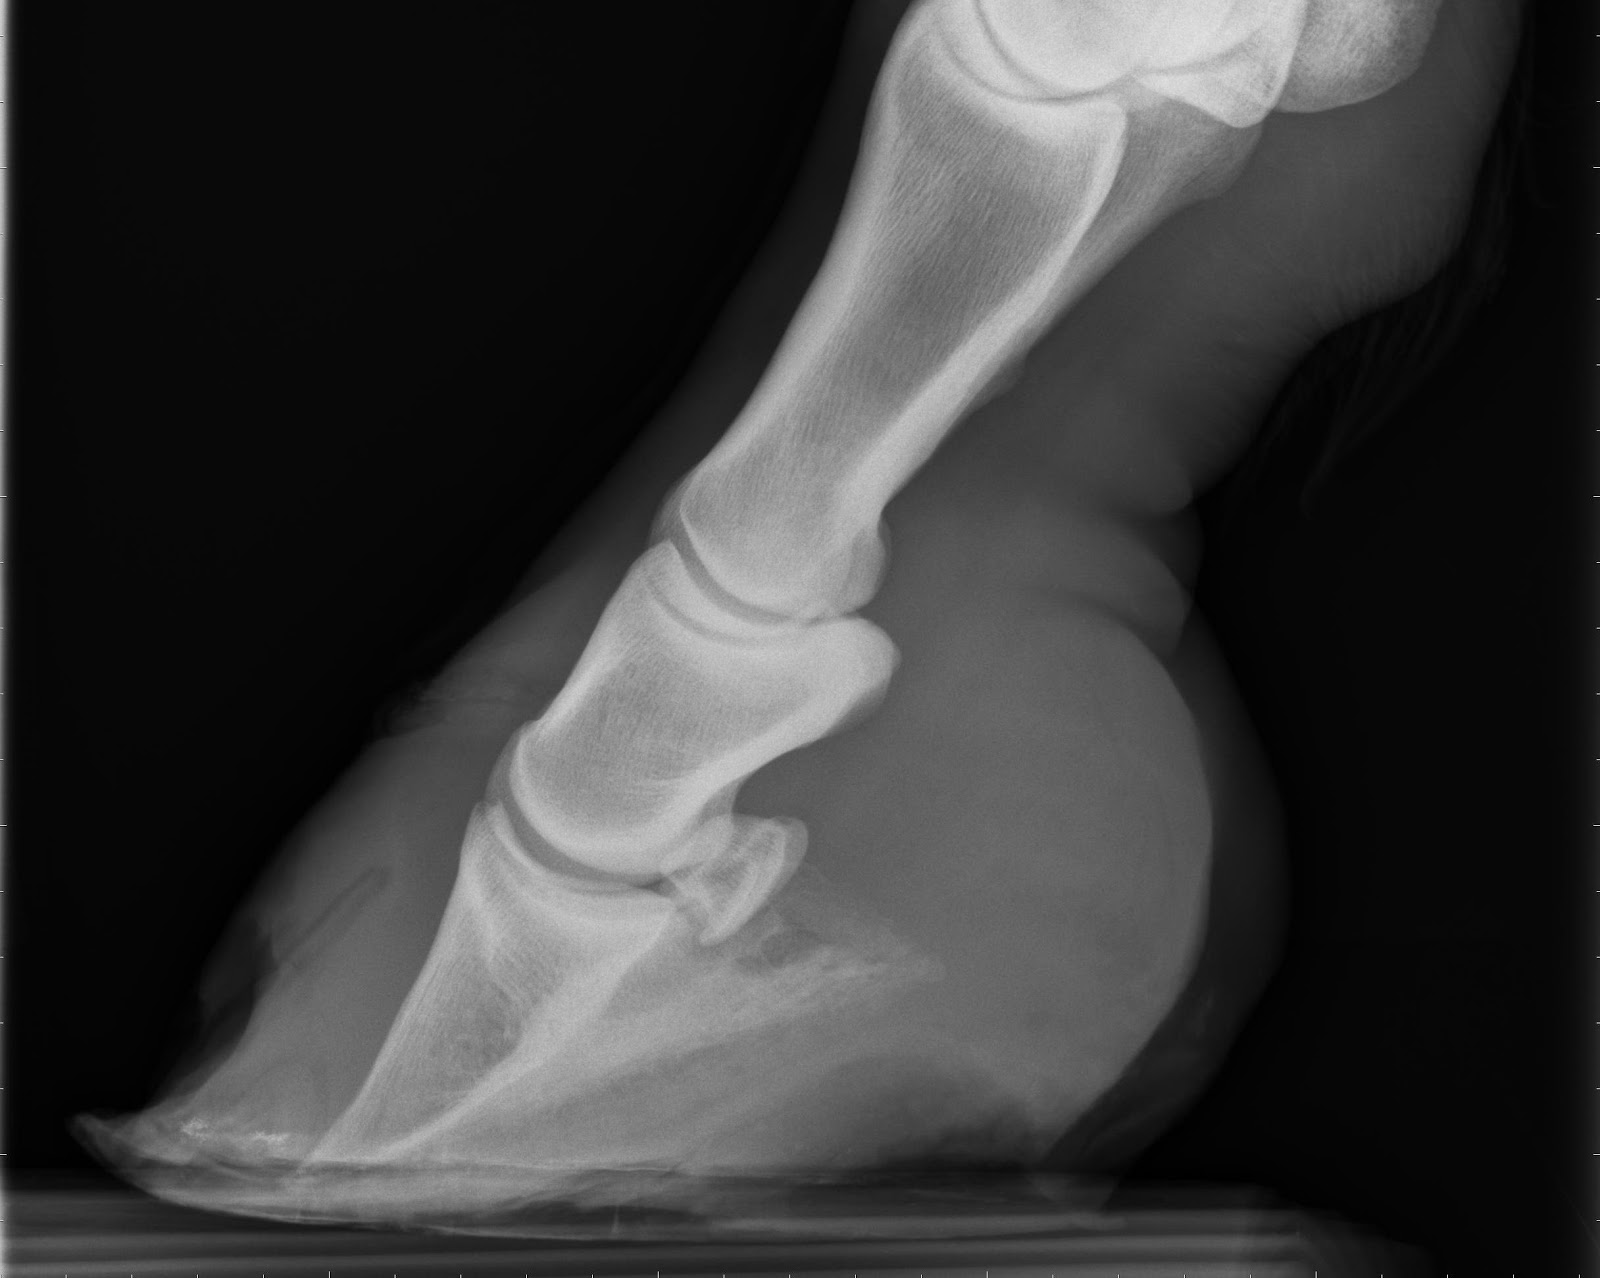

Una condizione collegata alla laminite è il rinfondimento, il rimodellamento del piede dovuto alla rotazione verso il basso dell'osso triangolare all'interno del piede del cavallo.

Rotazione della terza falange

La terza falange, nota anche come osso triangolare, ruota con la punta verso il basso. Normalmente, la terza falange dovrebbe essere parallela alla muraglia, ma nella laminite la tensione del tendine plantare profondo dovuta al dolore fa ruotare il triangolare. L'entità della rotazione dipende spesso dal ritardo con cui si fa diagnosi di laminite in un cavallo, e da quanto precocemente si praticano le cure.

Penetrazione della terza falange nella suola

Se la rotazione della terza falange continua, alla fine la sua punta può perforare la suola dello zoccolo. Ne consegue che il cavallo va in uno stato di shock, e dev'essere soppresso.

Importantissimi sono la diagnosi precoce, la terapia farmacologica e la cura del piede (mascalcia) e determinante è il grado di rotazione della III falange, se questo è < di 5° la progosi è favorevole per il completo recupero anche agonistico del cavallo, se >12° è infausta per l'utilizzo del cavallo; in una situazione intermedia permette all'animale di essere montato ma ne compromette la carriera agonistica.